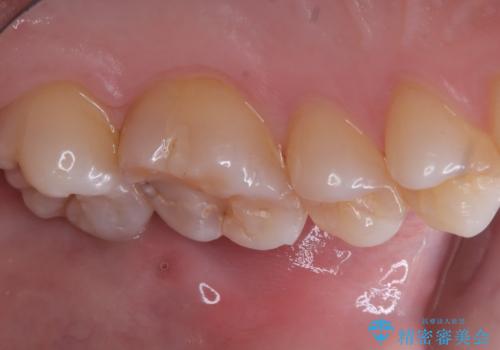

咬合面に穴が空き、歯の中でう蝕が広がっていました。この歯が過去に咬合面う蝕を経験しCR修復を受けていること、今回歯質とCRの境目からの二次う蝕になっていることを説明し、適合や材料安定性の良いセラミックインレーでのやり替えとなりました。

セット時はラバーダム防湿を行っています。